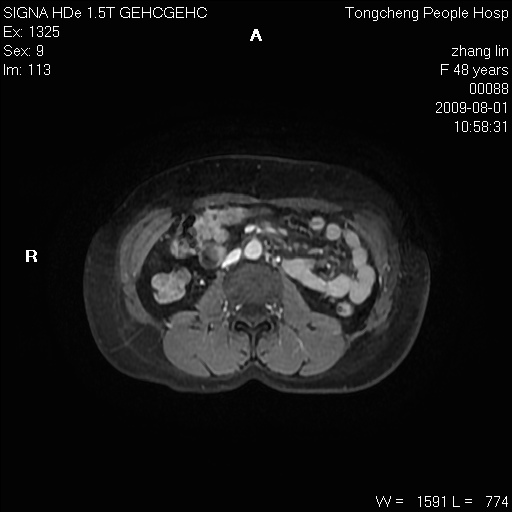

女,48岁。健康体检,彩超发现右肾占位性病变。平素健康。

临床诊断:右肾占位性病变,性质待定(囊肿?肿瘤?)。

上中腹部mr平扫+增强扫描,图像如下:

右肾上极见一类圆形病灶,t1wi呈等信号t2wi呈等高混杂信号,三期增强无强化,边界清---考虑囊肿出血。

同反相位均表现为等信号,病变无强化,考虑含蛋白的囊肿可能,弥散加权相或许有些帮助,

肝囊肿

慢性胆囊炎